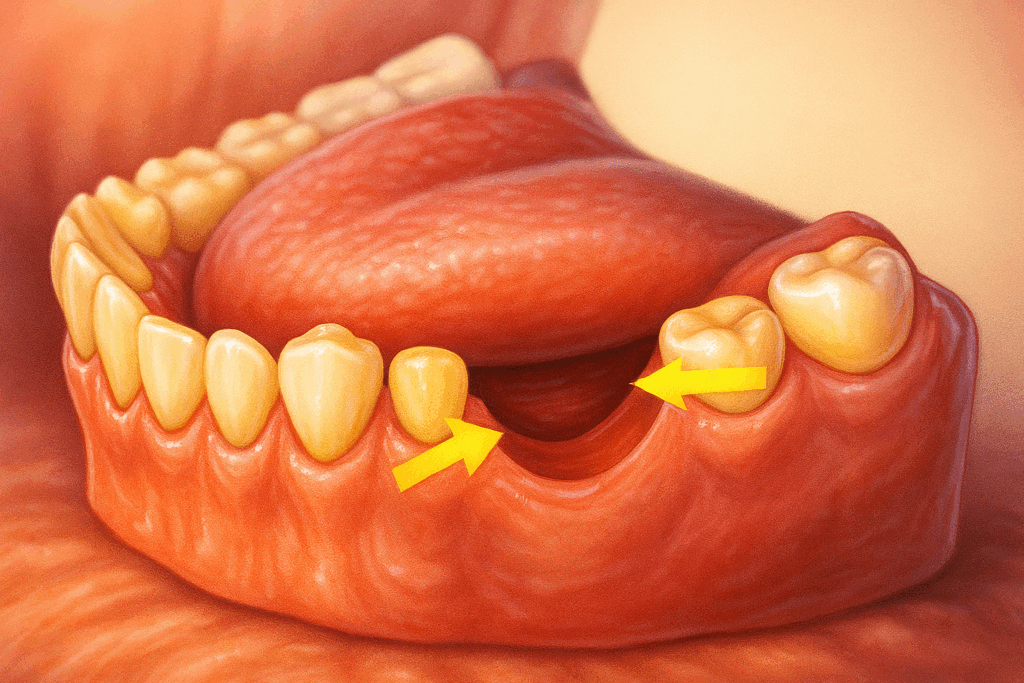

2. 치아 결손

민락 치과 에서 설명해 드린

충치가 진행된 어금니 외에도

눈에 띄는 부위가 있습니다.

그 앞쪽으로 결손된 곳으로,

텅 비어 있는 모습이 확인됩니다.

인접한 잇몸 조직에 비해서

다소 움푹 패인 모습을 보여주는데

이것은 치아가 결손된 부위가

그대로 방치된 케이스들에서

공통적으로 나타나는 문제입니다.

그건 바로 ‘골흡수’로

잇몸 조직이 자극을 받지 못하면

서서히 얇고 낮은 상태로 변합니다.

그로 인해 인접치에도 흔들림이 생기거나

주변 치아들이 이동하는 경우도 있습니다.

따라서 이 부위는 그대로 방치하는 것보다

기능적인 회복을 하는 것이 좋습니다.